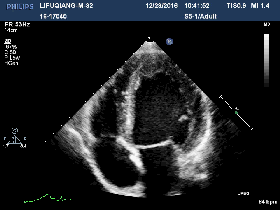

◆2016-11-24心超:

◆左房增大,左室增大;

◆左室壁整体收缩活动度下降,LGE显像提示整个心室壁心肌未见延迟强化现象,故可排除缺血性心肌病

◆LGE显像也未见类似限制性心肌病的特征性心内膜下延迟强化现象。

◆左室内多发条形信号影;LGE扫描未见强化,考虑血栓可能性大。